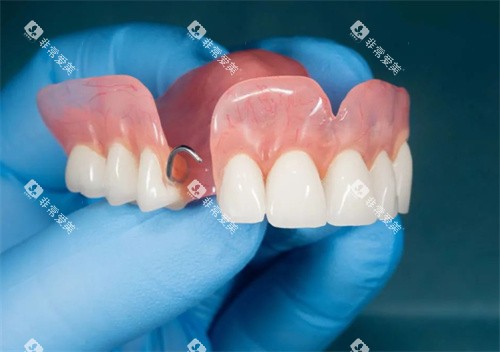

对于不适合种植牙的患者,传统修复方式也可通过优化设计来应对牙槽骨萎缩的问题。

活动假牙可通过特殊设计提高在萎缩牙槽骨上的固位和稳定性。例如增加基托的面积和贴合度,使用弹性义齿材料,或采用精密附着体等方式减少假牙在咀嚼过程中的晃动。重要的是,活动假牙的基托可以弥补萎缩的牙槽嵴,改善部分面部外观。